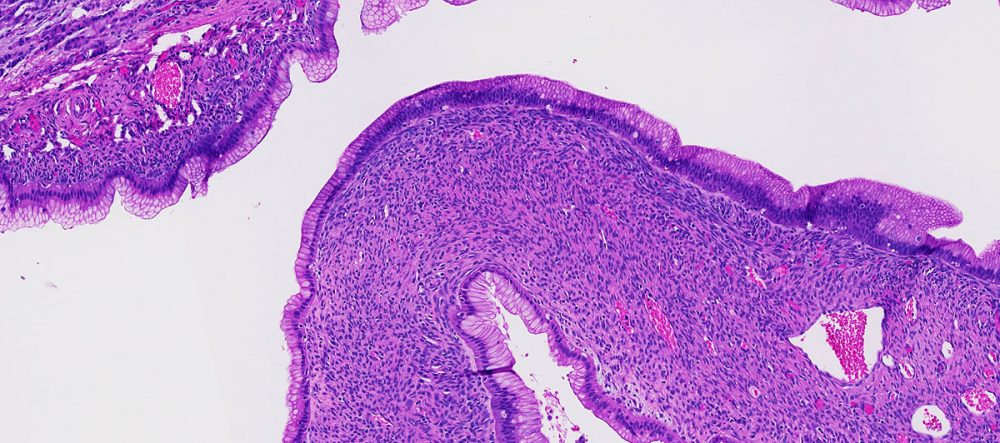

A term used to describe certain tumors which grow in finger-like projections. Pathologists use this term to describe some precancerous lesions in the pancreas (intraductal papillary mucinous neoplasm).

A term used to indicate that cancerous cells are present in the duct but have not yet invaded deeper tissues.

A benign (non-cancerous) tumor made up of cells that form glands (collections of cells surrounding an empty space).

The form of cancer that most people are talking about when they refer to "cancer of the pancreas." These tumors account for 75% of all pancreas cancers.

Microscopically, adenocarcinomas form glands. These tumors can grow large enough to invade nerves which can cause back pain. They also frequently spread (metastasize) to the liver or lymph nodes. If this happens the tumor may be considered unresectable.